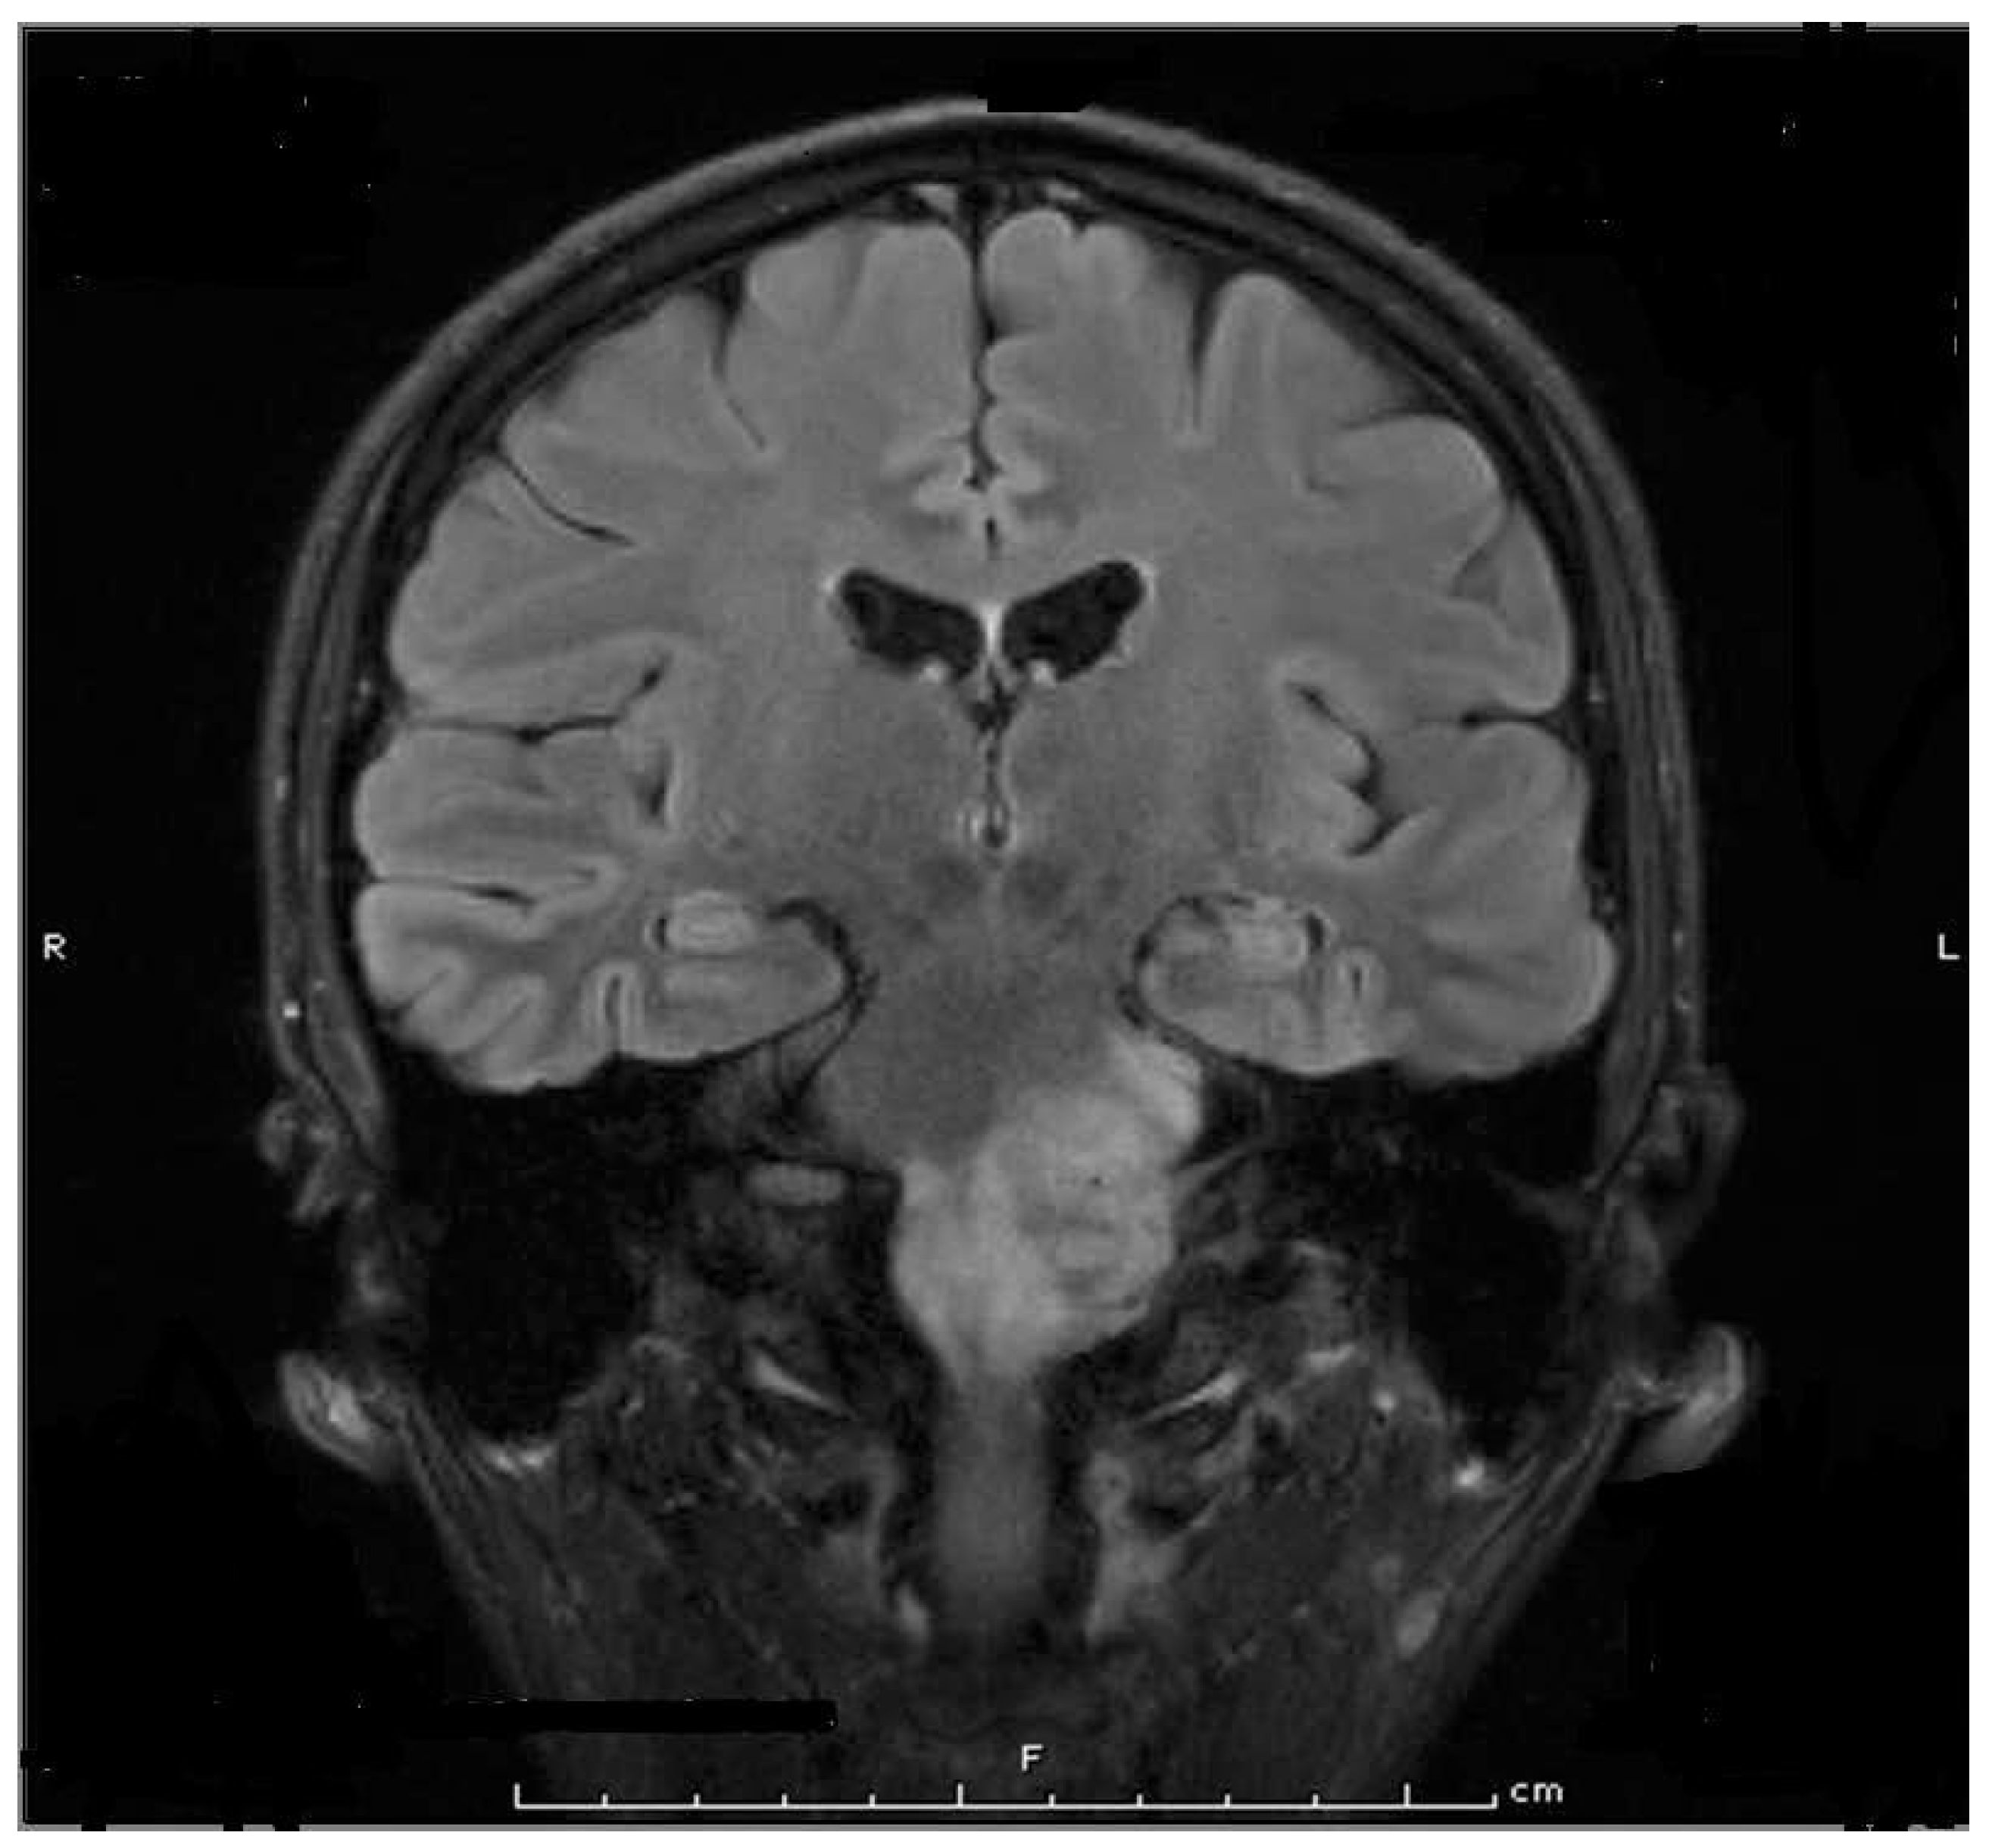

- Mueller, J.; Langbein, T.; Mishra, A.; Baum, R.P. Safety of High-Dose Botulinum Toxin Injections for Parotid and Submandibular Gland Radioprotection. Toxins 2022, 14, 64. [Google Scholar] [CrossRef]

| Mueller et al., 2022 [70] | Pro | 10 | Prostate cancer Post Ac-PSMA therapy | face | IncoA, 6 injections, 30 u per injection point | Those injected by BoNT showed a mean of 29% gland destruction after two cycles of Ac-PSMA treatment compared 60–70% seen in those who did not receive BoNT injection |